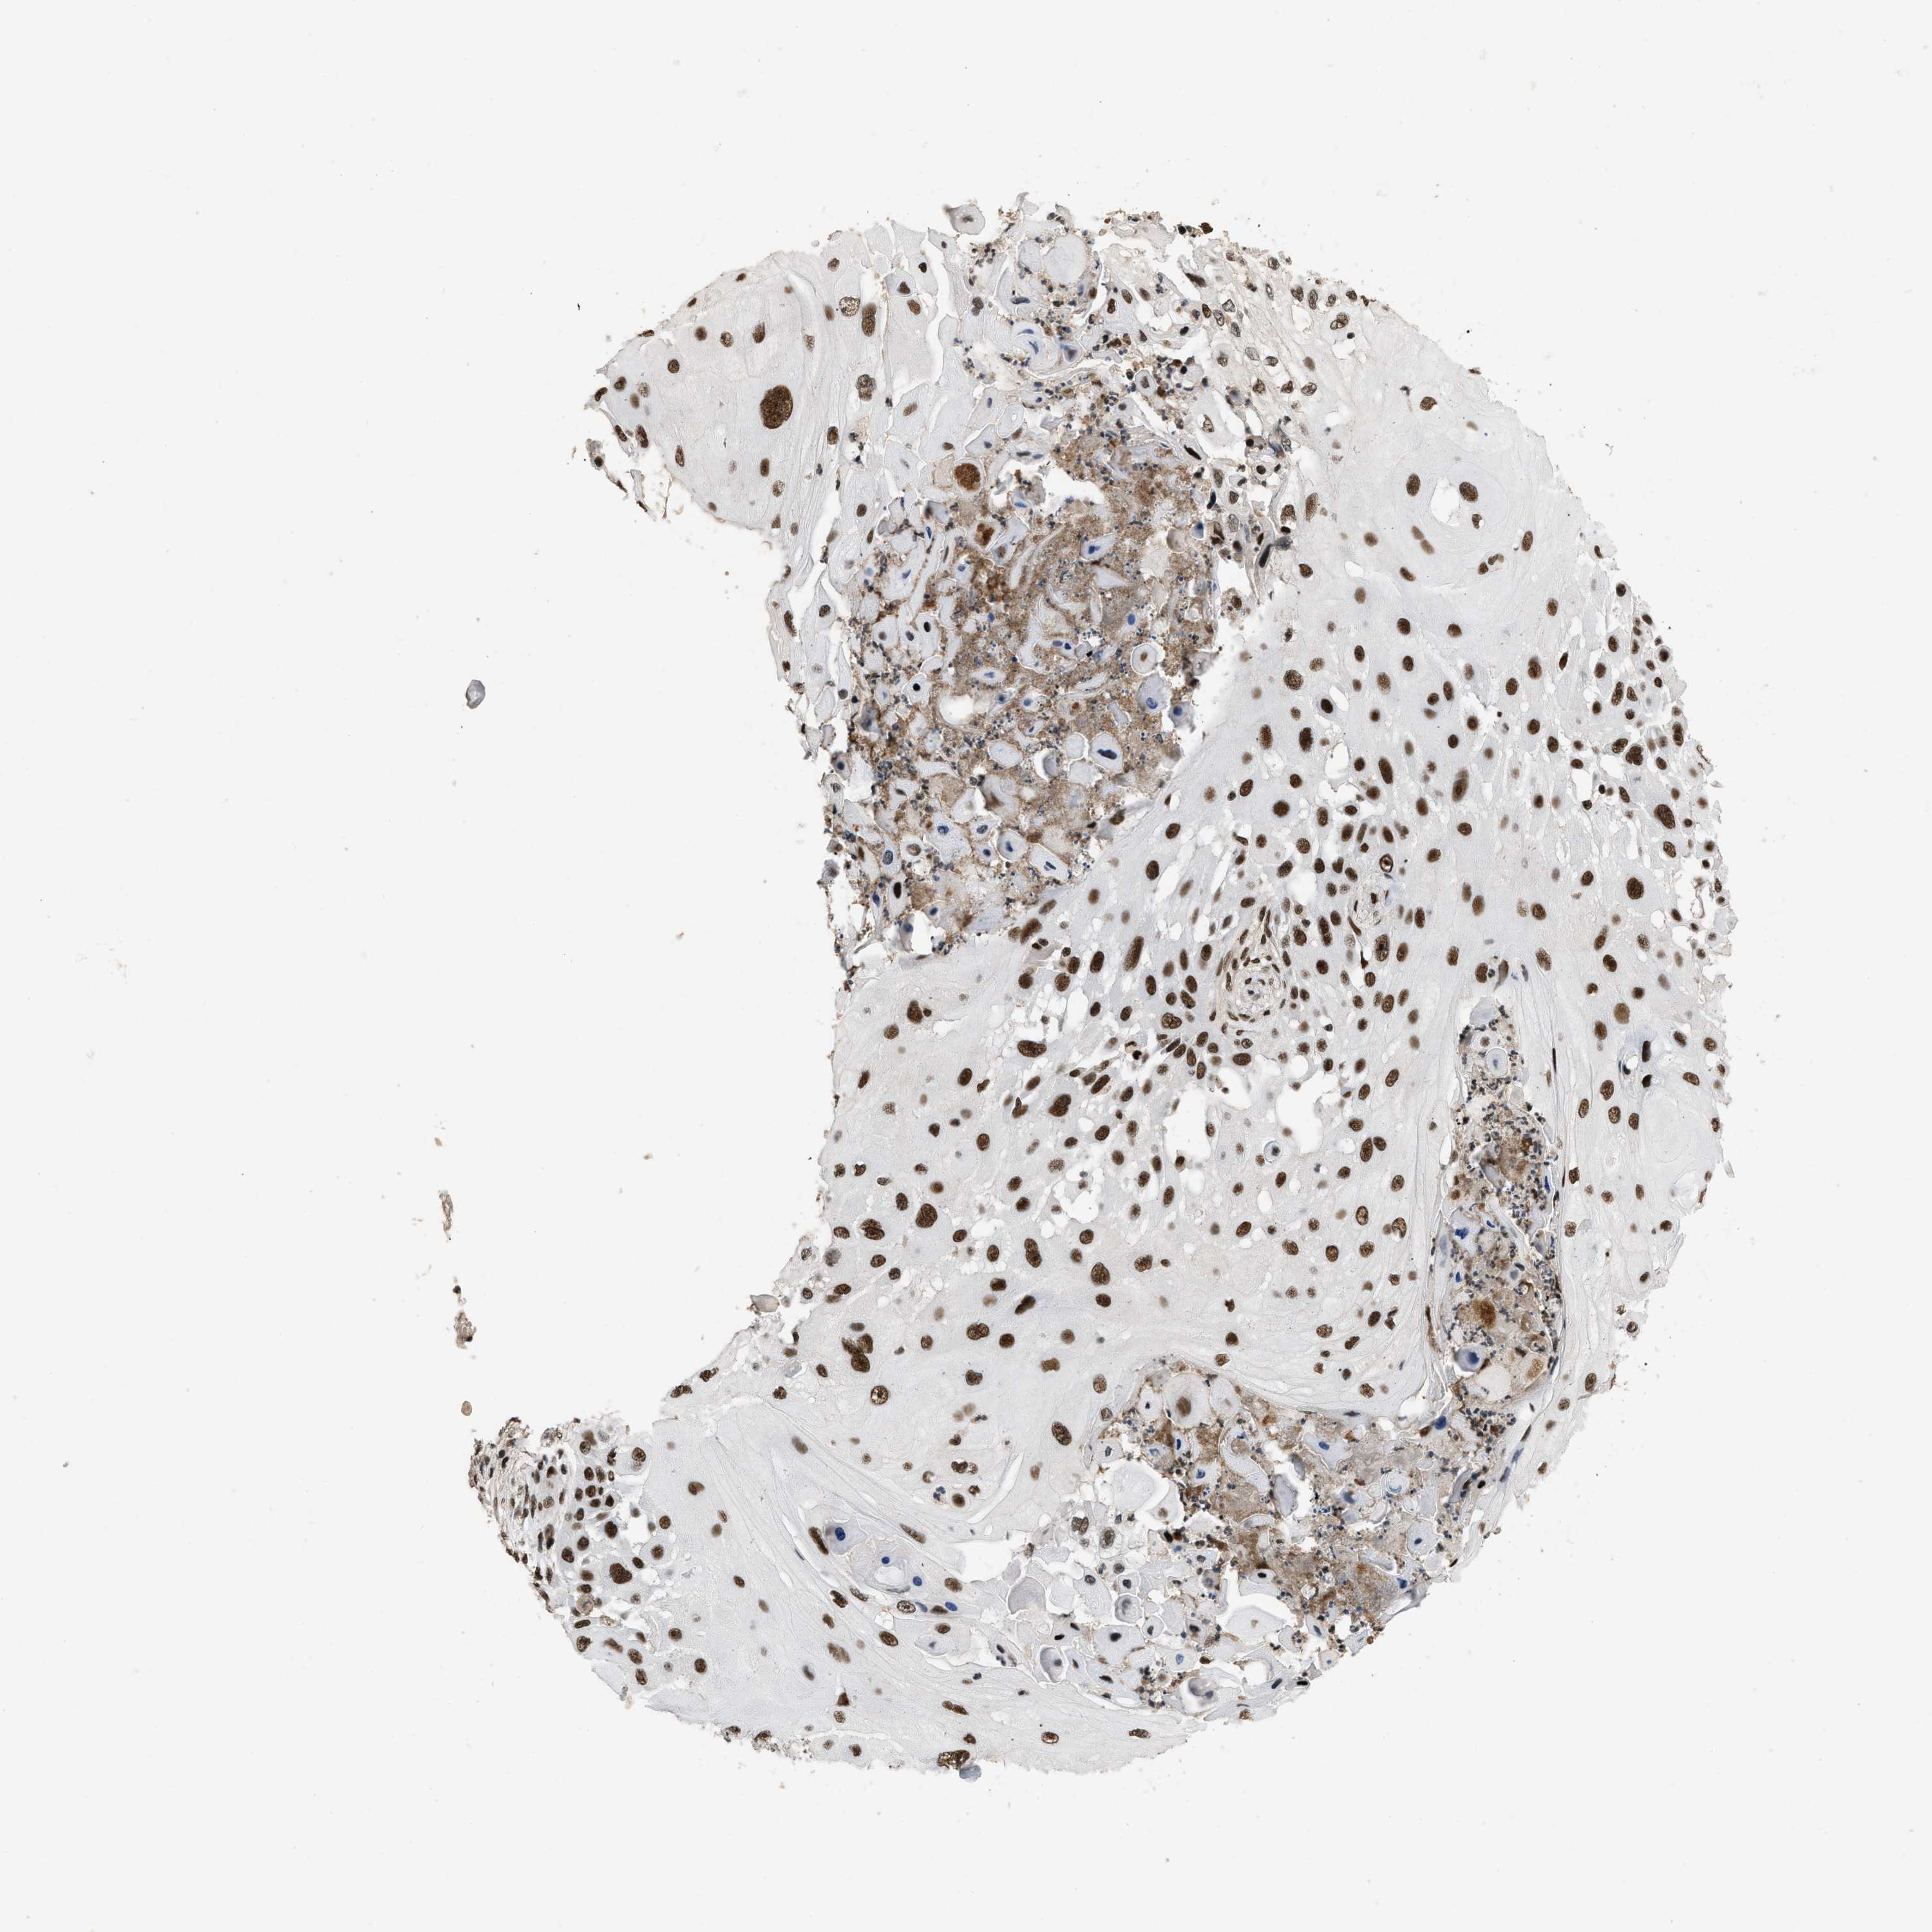

SKIN CANCER - Protein expressioni

A mouse-over function shows sample information and annotation data. Click on an image to view it in a full screen mode. Samples can be filtered based on level of antibody staining by selecting one or several of the following categories: high, medium, low and not detected. The assay and annotation is described here.

Each image is clickable and will lead to virtual microscopy that enables deeper exploration of all samples and also displays staining intensity scores, fraction scores and subcellular localization as well as patient and tissue information for each sample.

Antibody HPA018248

Squamous cell carcinoma in situ, NOS